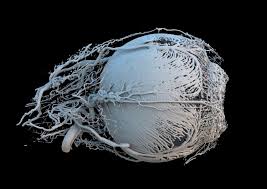

Những bức ảnh về khoa học nhưng không kém phần nghệ thuật của Giải thưởng Wellcome Image

Mạch máu trong mắt lợn. |